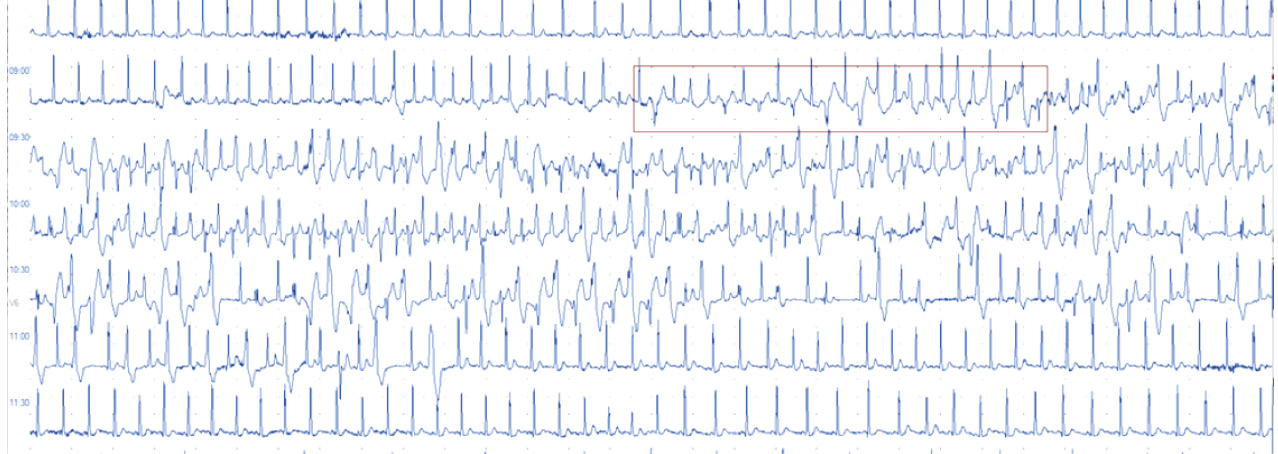

From the medical history, it is known that in two brothers (Patient 1 and Patient 2), the manifestation of the disease occurred at the age of 3 years in the form of syncope during physical exertion. The diagnosis was established based on Holter monitoring, which recorded exercise-induced bidirectional ventricular tachycardia (Fig. 1). Upon routine examination in both cases, additional findings included bradycardia and atrioventricular dissociation. Following diagnosis, specific antiarrhythmic therapy with atenolol at a dose of 1 mg/kg/day was prescribed. Medication compliance was regular and monitored by the children's parents. Due to progressive bradycardia, and with the aim of maintaining optimal beta-adrenergic blocker therapy doses, an implantation of a pacemaker was performed in both patients. Despite regular intake of antiarrhythmic therapy (atenolol at a dose of no less than 1 mg/kg/day), syncopal episodes recurred in both cases at a frequency of several times a year. Considering the occurrence of these events, despite optimal medical therapy, implantation of a cardioverter-defibrillator (ICD) was strongly recommended for preventing SCD. However, parents declined the recommendation. SCD occurred in the older brother (Patient 1) at the age of 14 years; parents had noted increased anxiety and emotional lability in the child before the event.

Fig. 1. A fragment of the 24-hour electrocardiographic monitoring: background sinus tachycardia with a heart rate of 121 bpm and polymorphic ventricular extrasystoles with transformation into polymorphic ventricular tachycardia (the beginning of the episode in the red frame), with subsequent bidirectional ventricular tachycardia of 6 sec duration; later on, bidirectional ventricular tachycardia gives way bigeminal ventricular extrasystoles and restoration of the sinus rhythm with a heart rate of 100 bpm